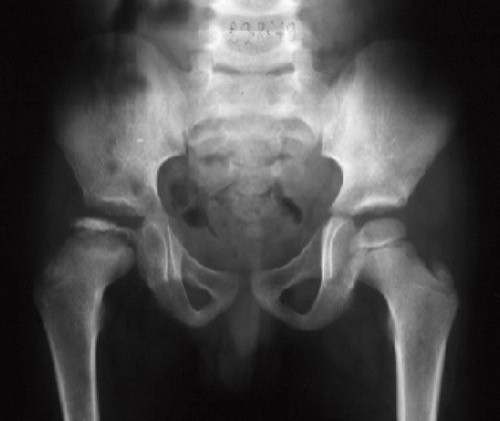

Røntgenbilder av hoftene i frontal- og sideprojeksjoner er fremdeles standard når det gjelder diagnostikk, med vurdering av nekrosens utbredelse, monitorering av forløp og evaluering av restdeformitet og leddkongruens.

Uavhengig av nekrosens utbredelse gjennomgår hofteleddet forskjellige røntgenologiske faser (12). Initialfasen er karakterisert ved forandringer i epifysens høyde, bredde og beinstruktur. I den påfølgende fragmenteringsfasen er epifysen helt eller delvis resorbert, med et typisk fragmentert utseende (fig 1). Siden går hoften gjennom tilhelingsfasen (reossifiseringsfasen).

Ved femur- eller bekkenosteotomi sentreres caput femoris i acetabulum der det nekrotiske caput i fragmenterings- og gjenoppbyggingsfasen kan formes av acetabulum, slik at det blir mest mulig sfærisk ved tilheling (28, 29). Figur 4 viser et eksempel på en hofte ved Calvé-Legg-Perthes’ sykdom før og etter proksimal variserende femurosteotomi. Bekkenosteotomi synes å ha fått økende anvendelse internasjonalt. Flere studier har vist at denne behandlingen gir tilsvarende resultater som ved femurosteotomi (30, 31). Bekkenosteotomi utføres sjelden i Norge på denne indikasjonen og ble derfor ikke evaluert i den norske studien.